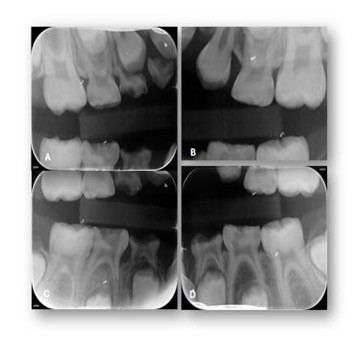

Figure 3: Selected periapical radiographs. A-D) According to the AAPD Guidelines for Prescribing Dental Radiographs, when evaluating a new patient in the mixed-dentition stage for dental disease and developmental assessment, an individualized radiographic examination should include a panoramic radiograph supplemented by posterior bitewings and selected periapical images as indicated.

Figure 7: Post-Operative Selected periapical and bitewings radiographs. A-D) Post-operative views showing restored teeth, resolution of carious lesions, and improved periapical status following treatment.